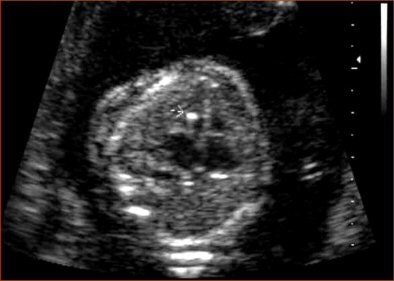

At times ethnicity can have a significant bearing on the weightage given to a marker, as is the case with echogenic intracardiac foci (EIF). "The incidence of EIF in Asian mothers is higher than those seen in fetuses with Down syndrome.... In low-risk women, the presence of EIF does not warrant further testing, especially in Asian population," Suresh said.

EIF is commonly observed as a single focus in the left ventricle.

| Echogenic intracardiac focus (arrow). |

As compared to the CP cysts and hyperechoic bowel, EIF is a fairly common finding at 3% to 10% of the population. However, less than 20% of aneuploid fetuses have EIF. Chances of aneuploidy are greater if EIF is seen in both ventricles.